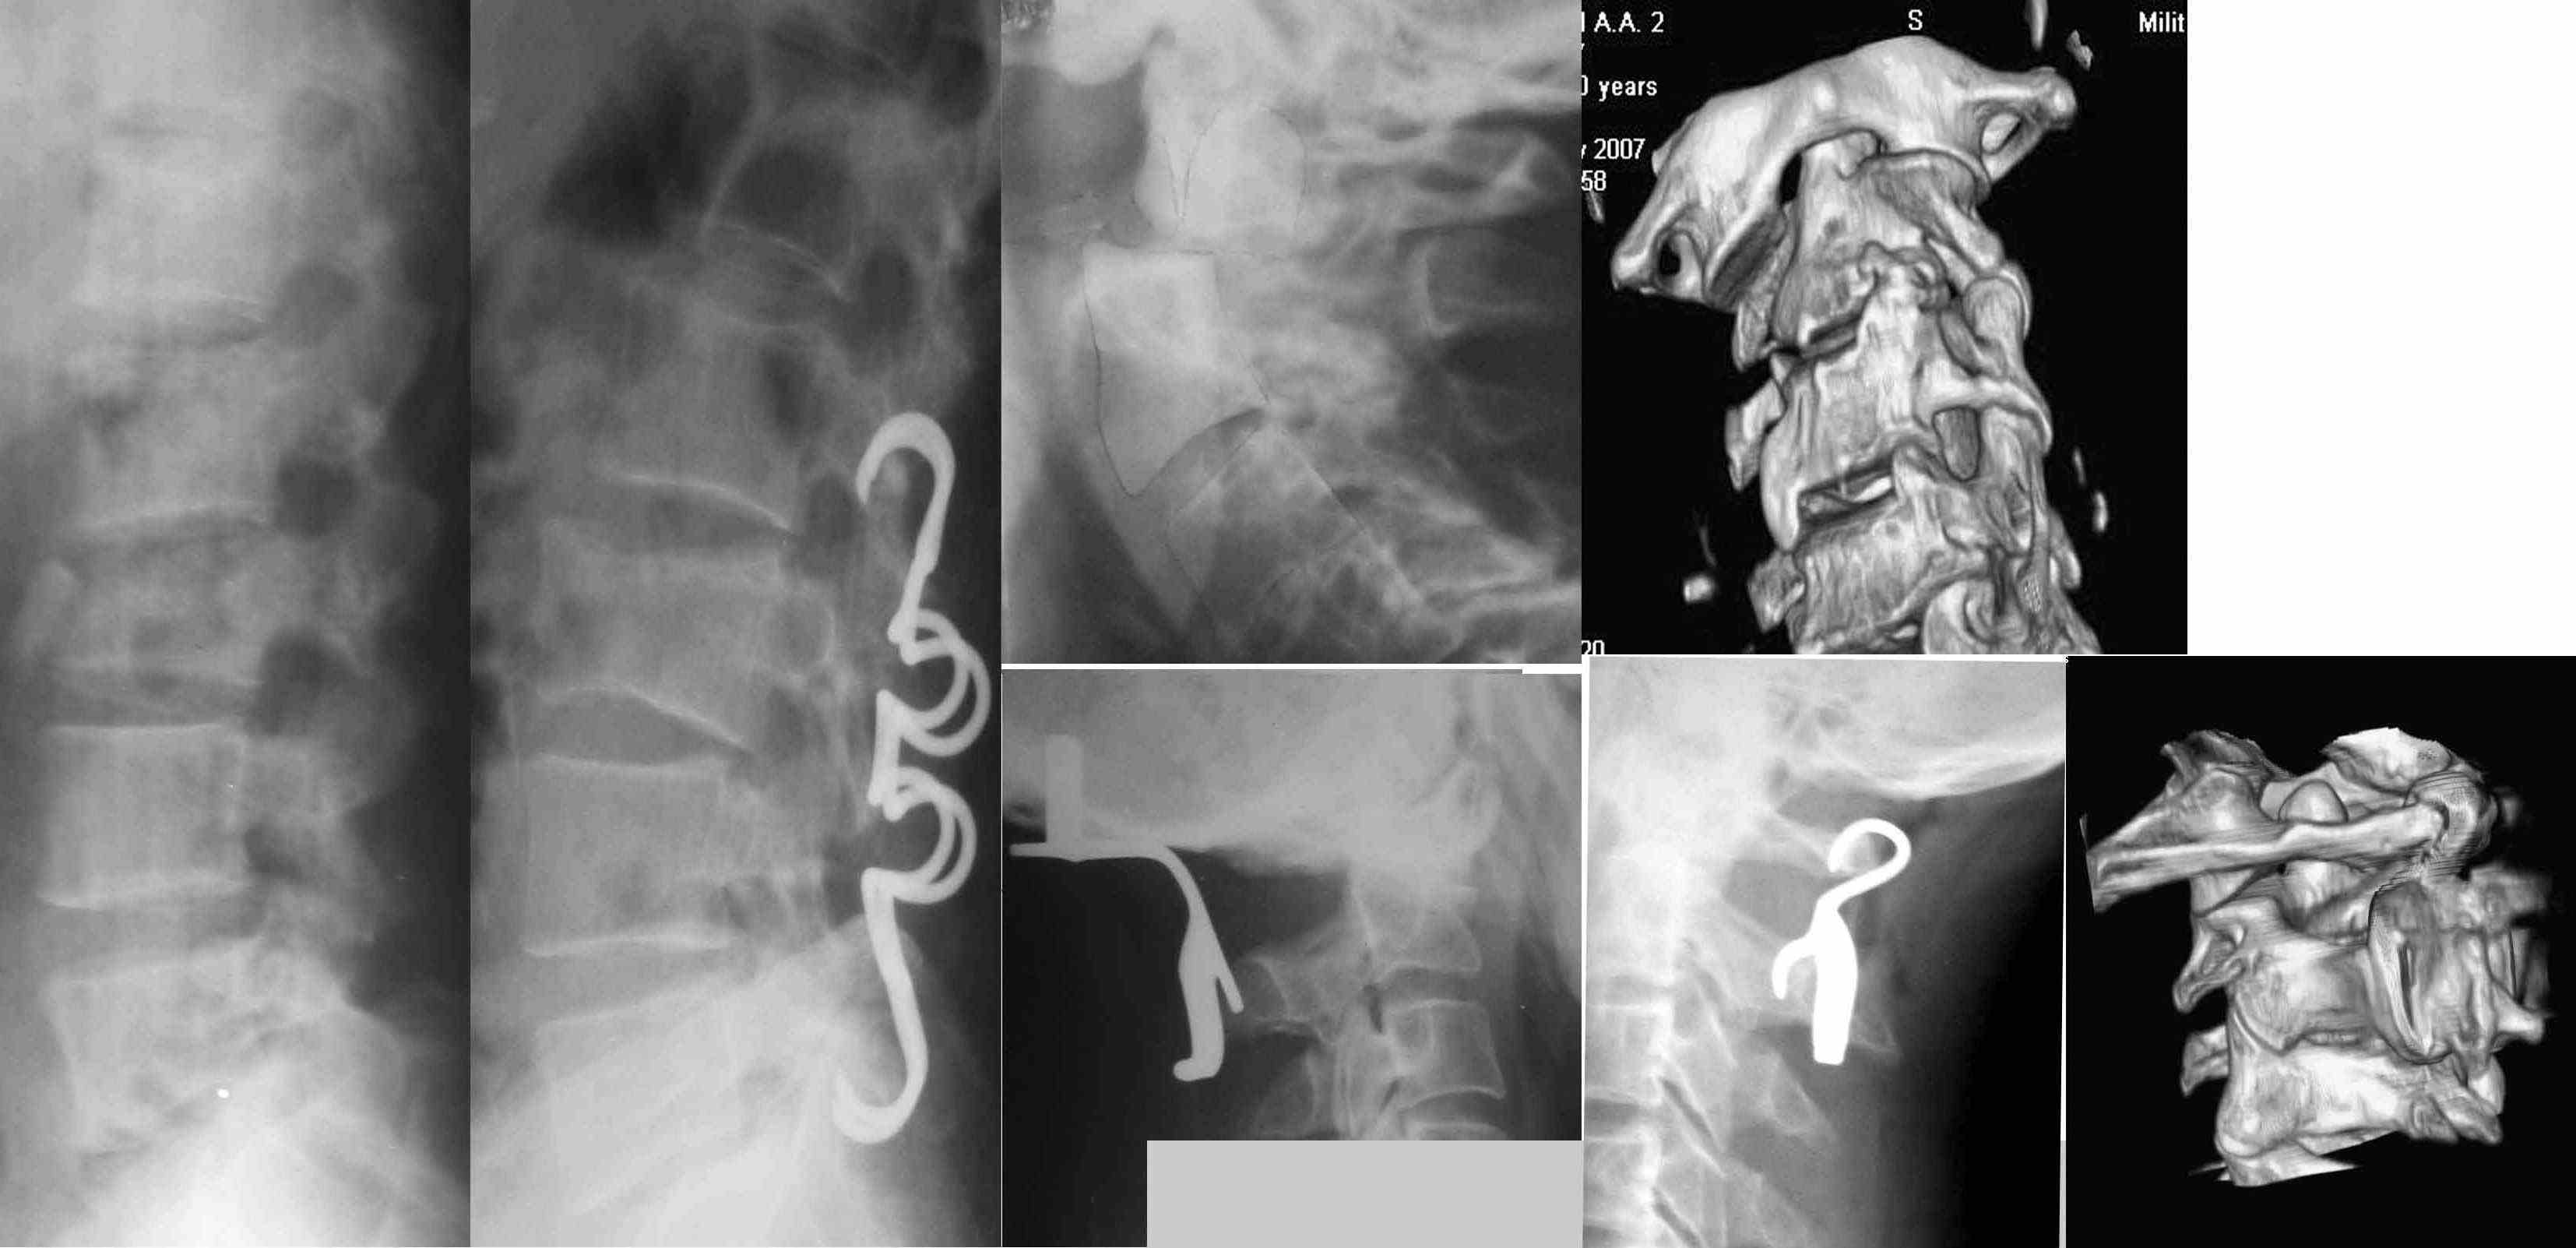

Использую имплантанты с ТМПФ с 2002 года. Как и любой метод при хорошем знании правил его применения дает хорошие результаты. Фактически все металлокоснтрукции с ТМПФ при остеосинтезе трубчатых костей выполняют "вспомогательную" роль блокирующих конструкций(т.е. ограничивают смещение по длине и ротацию) + создают межотломковую компрессию. Это не исключает необходимотсь дополнительной установки "несущей" нагрузку конструкции (штифта, аппарата). В скобах для остеосиентеза ключицы и локтевого отроска "несущий" элемент включен в конструкцию.

Достаточно удобны скобы для задней динамической фиксации позвоночника.

Действительно уникальные конструкции, не имеющие аналогов - это скобы для окципитоспондилодеза и атланто-аксиального спондилодеза.